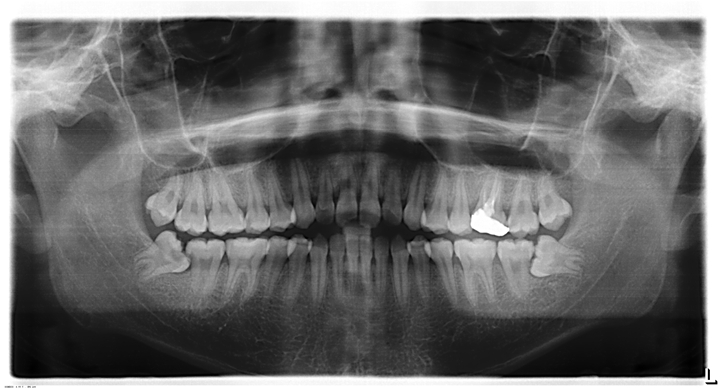

(»çÁø - 2)

±×·¯³ª »ç¶û´Ï°¡ °ø°£ÀÌ ºÎÁ·ÇÏ¿© ÀϺθ¸ ³ª¿À°í ÀϺδ ÀÕ¸ö »À¿¡ ¹¯È÷´Â(»çÁø 1) °æ¿ì³ª ¶§·Î´Â ¹Ù·Î ¾Õ ¾î±Ý´Ï(Á¦2´ë±¸Ä¡)¿¡ °É·Á¼ ´õ ÀÌ»ó ¸ÍÃâÇÏÁö ¸øÇÏ°í ¾Õ´Ï ÈĸéÀ» ¾Ð¹ÚÇÏ´Â ÇüÅ·Π´©¿ö ÀÖ´Â ¼öÆòÁöÄ¡(»çÁø 2) ÇüÅ·Π³ª±âµµ ÇÕ´Ï´Ù.